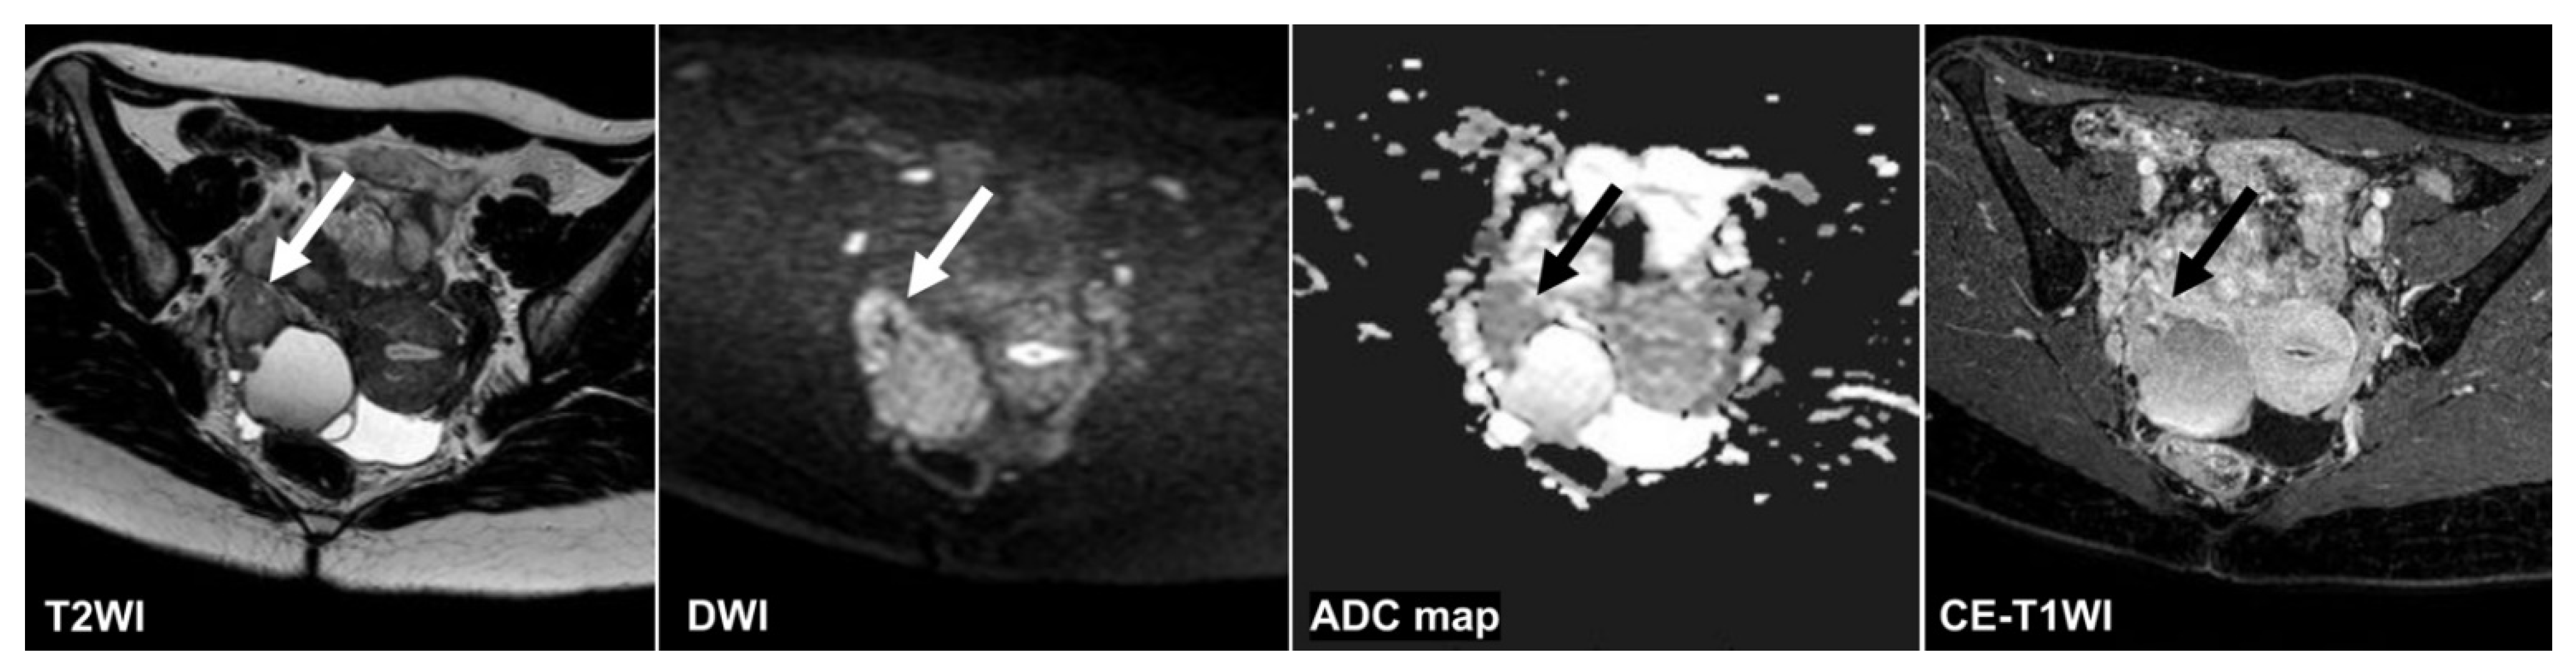

Figure 6.

A 28 year old woman with high-grade serous carcinoma. None of the CNNs or the three radiologists could diagnose malignant tumors on the T2WI and the ADC map (CNN confidence value: malignant = 0.0% on the T2WI; malignant = 1.5% on the ADC map). Only reader 3 could diagnose a malignant tumor on the CE-T1WI (CNN confidence value: malignant = 0.0%). In contrast, the CNN and all radiologists could diagnose malignant tumors on the DWI (the CNN confidence value; malignant = 99.9%). It seemed it was difficult to distinguish the tumor (arrow) from the intestinal tract. ADC: apparent diffusion coefficient; CE-T1WI: contrast-enhanced T1-weighted imaging; CNN: convolutional neural network; DWI: diffusion-weighted imaging; T2WI: T2-weighted imaging.